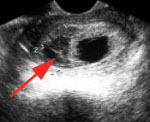

O20.8 Другие кровотечения в ранние сроки беременности